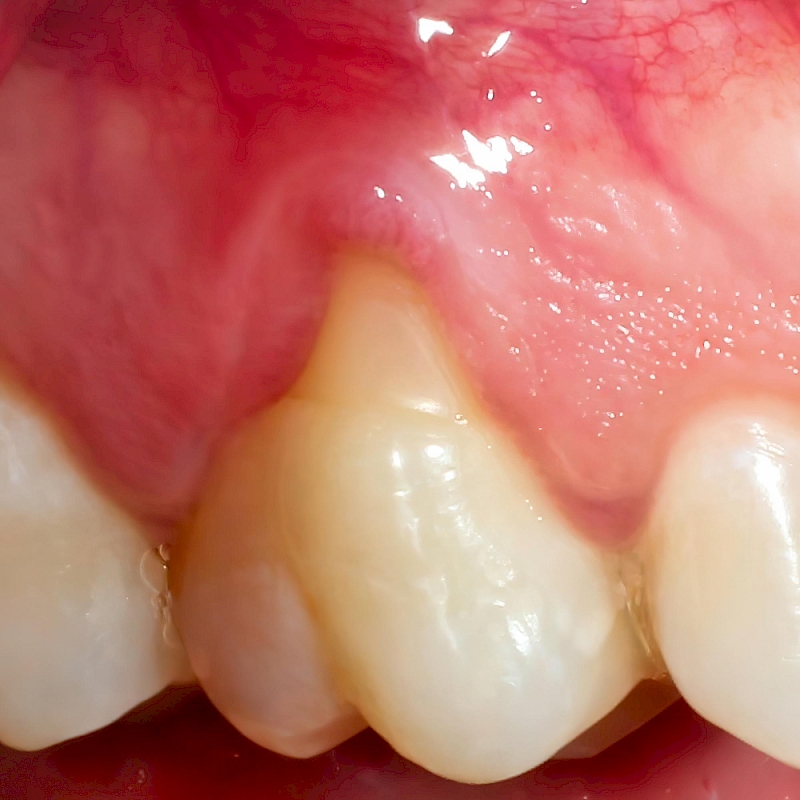

Gingival recession is more common, especially in people with thin gums. Apart from this, gingival recessions, are caused by tartar accumulation, excessive tooth clenching habit, hard and faulty tooth brushing, activation of the gum by the lip and cheek muscle ligaments and excessive forces seen during orthodontic treatment. In individuals with gingival recession, sensitivity to hot and cold, decays on the exposed root surface and aesthetic problems can be seen.

Today, the treatment of gingival recession has a very high success rate in the hands of physicians specialized in this field. The first step in the treatment of gingival recession is to determine the cause of the recession and to eliminate the factor. In the second stage, the root surface is covered with the appropriate surgical technique and the third stage is to motivate the patient in terms of oral care in the postoperative period.

The lost gum tissue is usually replaced by gum transplantation taken from the upper palate by integrating it into the area where the gum is extracted. At this stage, connective tissue grafts taken from the upper palate and free gum grafts are integrated into the root surface by the specialist physician with special micro-surgical and suture techniques. Gingival recession is repaired to provide an aesthetically correct appearance, to protect the opened tooth root surfaces again and to prevent gingival recession in that area by thickening the thin gums.